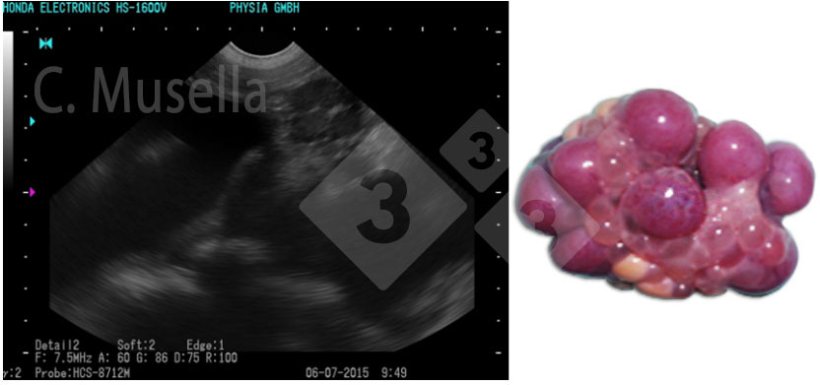

Figure 1. Corps jaune.